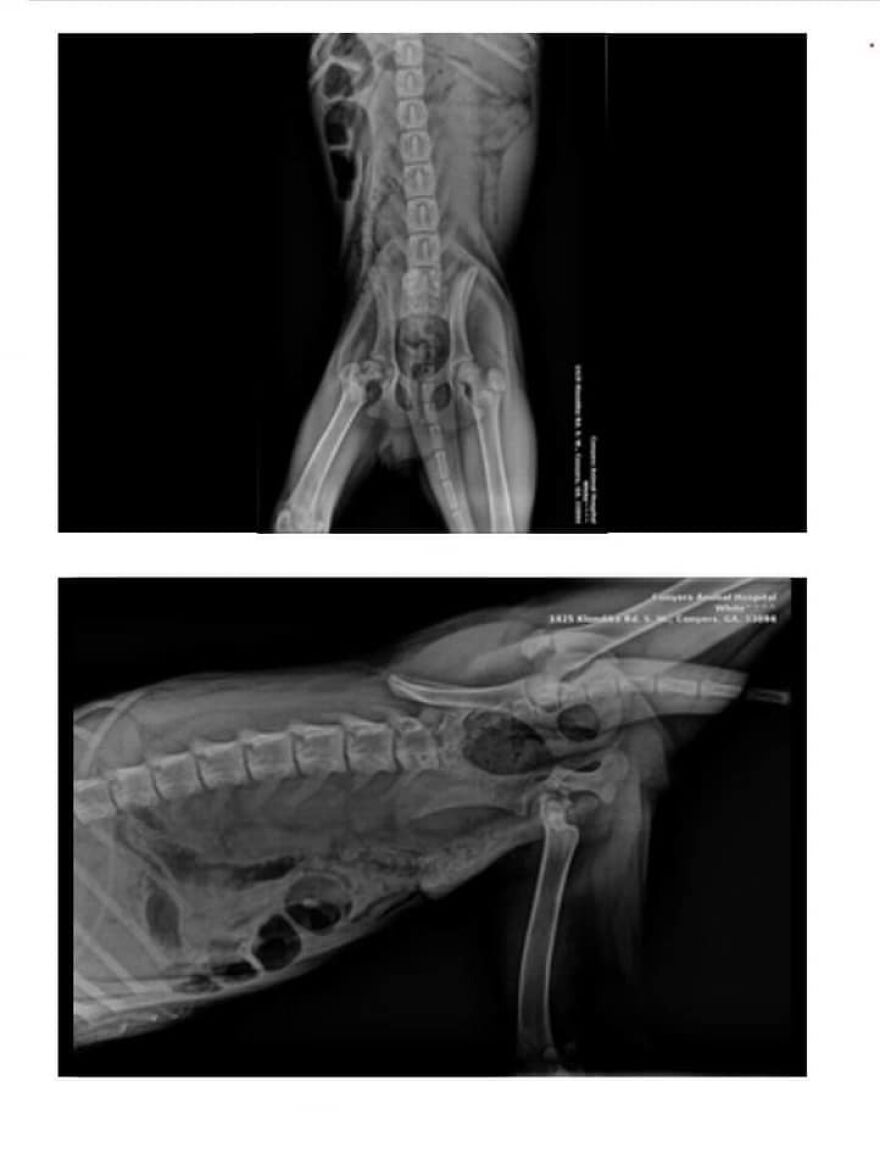

The Doctor found out that the Canine had his Leg broken for more than 2 weeks

Fracture so painful he couldn’t move. Hank’s injury required major surgery, so the shelter reached out to Humans and Animals United for help

Humans and Animals United shared on social media about the circumstances Hank was found in, adding, “Hank has been staying at the Veterinary Hospital to gain weight before surgery because he was so thin. The surgeon estimates that the leg was fractured for more than two weeks and that he was abandoned in the woods for two weeks.”

Broken leg was the reason why the puppy never considered moving from his bed in the woods